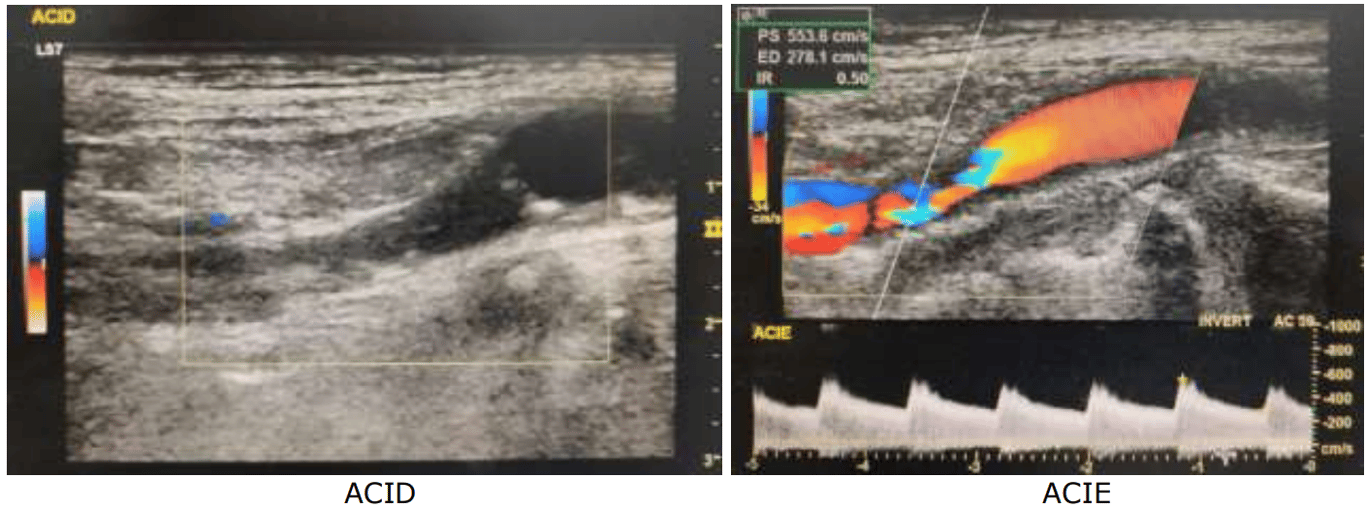

O índice de pulsatilidade é dado: